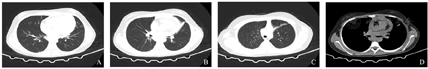

辅助检查:入院查血常规:白细胞计数16.65×109/L,嗜酸性粒细胞百分比30.4%,嗜酸性粒细胞计数4.99×109/L,血小板计数705×109/L。尿常规:酮体阳性(++++),潜血弱阳性(±),白细胞定量48个/μL,结晶475个/μL。凝血功能:FDP 33.23 μg/mL, D-D 12.5 μg/mL。肿瘤标记物:CA125 139 U/mL,人附睾蛋白469.0 pmol/L,铁蛋白237 ng/mL。25-羟维生素D 6.0 ng/mL。血细胞质量分析:中性分叶核粒细胞51%,嗜酸性分叶核粒细胞20%,成熟淋巴细胞28%,成熟单核细胞1%。腹水常规:颜色黄色,透明度微浑,凝固性无凝块,红细胞计数3 000×106/L,白细胞计数7 706×106/L,单个核细胞百分比9%,多个核细胞百分比91%,黏蛋白定性试验阳性(+);细胞学检查:有核细胞量多,以中性粒细胞为主,可见嗜酸性粒细胞(20%)、嗜碱性粒细胞(4%)。腹水生化:总蛋白43.4 g/L,碱性磷酸酶47.0 U/L,血糖4.79 mmol/L,乳酸脱氢酶218 U/L,腺苷脱氨酶6.3 U/L。腹水细菌涂片:未查到细菌。腹水细菌培养:无细菌生长。痰、尿、血培养:未见病原菌生长。骨髓涂片结果:未见任何异常细胞或寄生虫;粒系增生活跃,成熟嗜酸性粒细胞偏高占30%。骨髓活检结果:免疫组织化学:嗜酸性粒细胞增多,未见幼稚细胞及淋巴细胞增多,巨核细胞少见;流式细胞免疫荧光分析:CD34+细胞占有核细胞比例约0.50%,其免疫表型未见明显异常,粒细胞相对比例增多,其免疫表型CD13、CD15、CD16、CD11b未见明显表达紊乱,可见约40.6%的嗜酸性粒细胞;淋巴细胞相对比例减少,其中T细胞占淋巴细胞的72.0%,CD4∶CD8=1.77;NK细胞占淋巴细胞5.96%;成熟B淋巴细胞占淋巴细胞19.88%。骨髓染色体核型分析:46,XX,未见克隆样结构和数目异常。融合基因BCR/ABL、PDGFRB、PDGFRA、FGFR1、JAK2均阴性。寄生虫血清学检查:血吸虫、肺吸虫、囊虫、旋毛虫、肝吸虫、裂头蚴、包虫均未检出。过敏原检测均阴性。总IgE正常。粪便常规、生化全项、红细胞沉降率、降钙素原、T细胞亚群检测、免疫球蛋白、风湿二项、甲功五项、术前八项均正常。自身抗体全项、72 h结核菌素试验、结核γ干扰素实验、呼吸道病毒抗体8项均阴性。动态心电图监测未见明显异常。心脏彩超提示三尖瓣反流(少量)、心包积液(少量)。腹部彩超提示腹水大量,最大深度位于下腹部约73 mm。胸部CT提示:右肺散在结节;左肺上叶局限性肺不张;双肺多发索条;心包积液;双侧胸腔少量积液(图1)。全腹CT及泌尿系MRI+MRU提示:膀胱壁弥漫性不均匀增厚;腹膜弥漫增厚;腹盆腔大量积液;肠系膜根部、腹膜后、双侧腹股沟及髂血管旁多发肿大淋巴结(图2)。

A:右肺散在结节;B:左肺上叶局限性肺不张;C:双肺多发索条;D:心包积液,双侧胸腔少量积液。